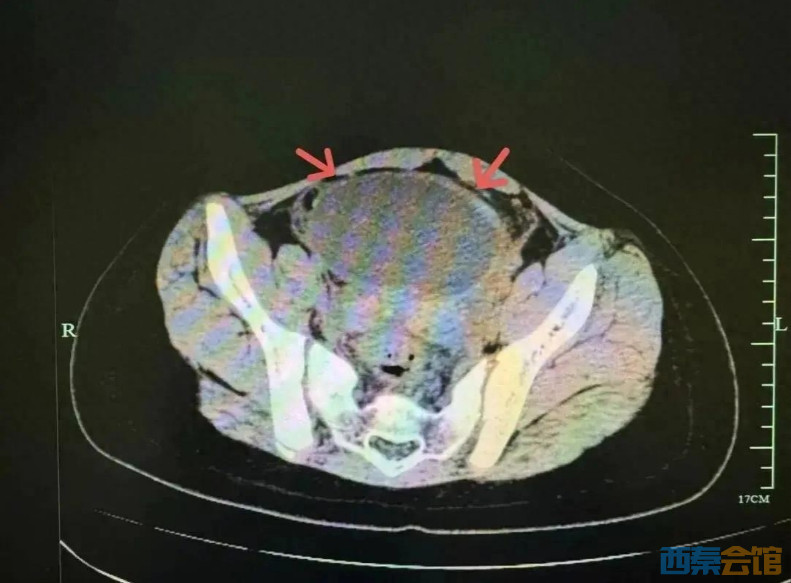

[盐都杂谈] 10岁女孩腹痛呕吐体内竟有硕大的卵巢囊肿……医生:女孩特别要注意

最近气温骤降,10岁的小吉突然闹起了肚子,又痛又吐,于是来到浙江省中西医结合医院儿科就诊,医生检查发现小吉血象高、B超提示肠系膜淋巴结肿大,类似儿童常见的急性胃肠炎及肠系膜淋巴结炎,医生进行了抗感染和对症治疗。治疗后小吉呕吐的情况好转了,但肚子还疼,复查感染指标反而更高了,医生立即进行了更深入的排查。